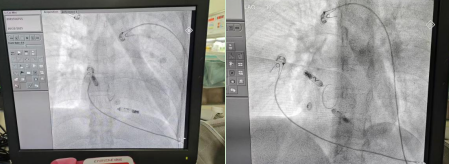

本次手术患者是一位 35 岁年轻女性,临床诊断为高度房室传导阻滞、先天性房间隔缺损。患者既往有阵发性房颤消融病史,以及右心室无导线起搏器植入史。经过医疗团队全面评估,该患者符合 AVEIR™ DR 双腔植入式无导线心脏起搏系统的植入指征,且无明显禁忌症。在与患者及其家属充分沟通后,团队决定施行 AVEIR™ DR 双腔植入式无导线心脏起搏系统的植入手术。

陈琦教授介绍:「手术分别在患者右心耳基底部和右心室低位间隔处植入一枚无导线起搏器,两者通过 i2i™通信技术进行配对,实现房室顺序起搏。该起搏系统支持灵活选择起搏模式,既可针对患者当前病情实施治疗,也为未来可能的病情进展预留了干预空间。」